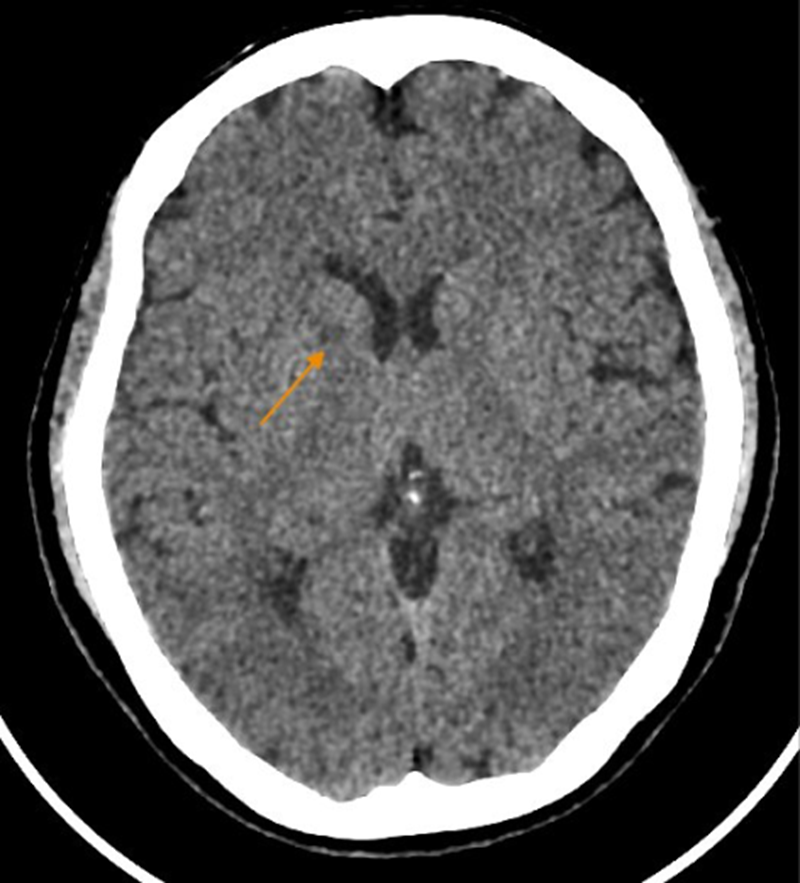

Chụp cắt lớp vi tính sọ não ghi nhận dấu hiệu bất thường

Chụp cắt lớp vi tính sọ não không tiêm thuốc đối quang (32 dãy) cho thấy xơ vữa vôi hóa động mạch cảnh trong hai bên đoạn xoang hang và động mạch đốt sống hai bên đoạn nội sọ. Chụp X-quang tim - phổi thường quy ghi nhận cung động mạch chủ giãn nhẹ, kèm vôi hóa.